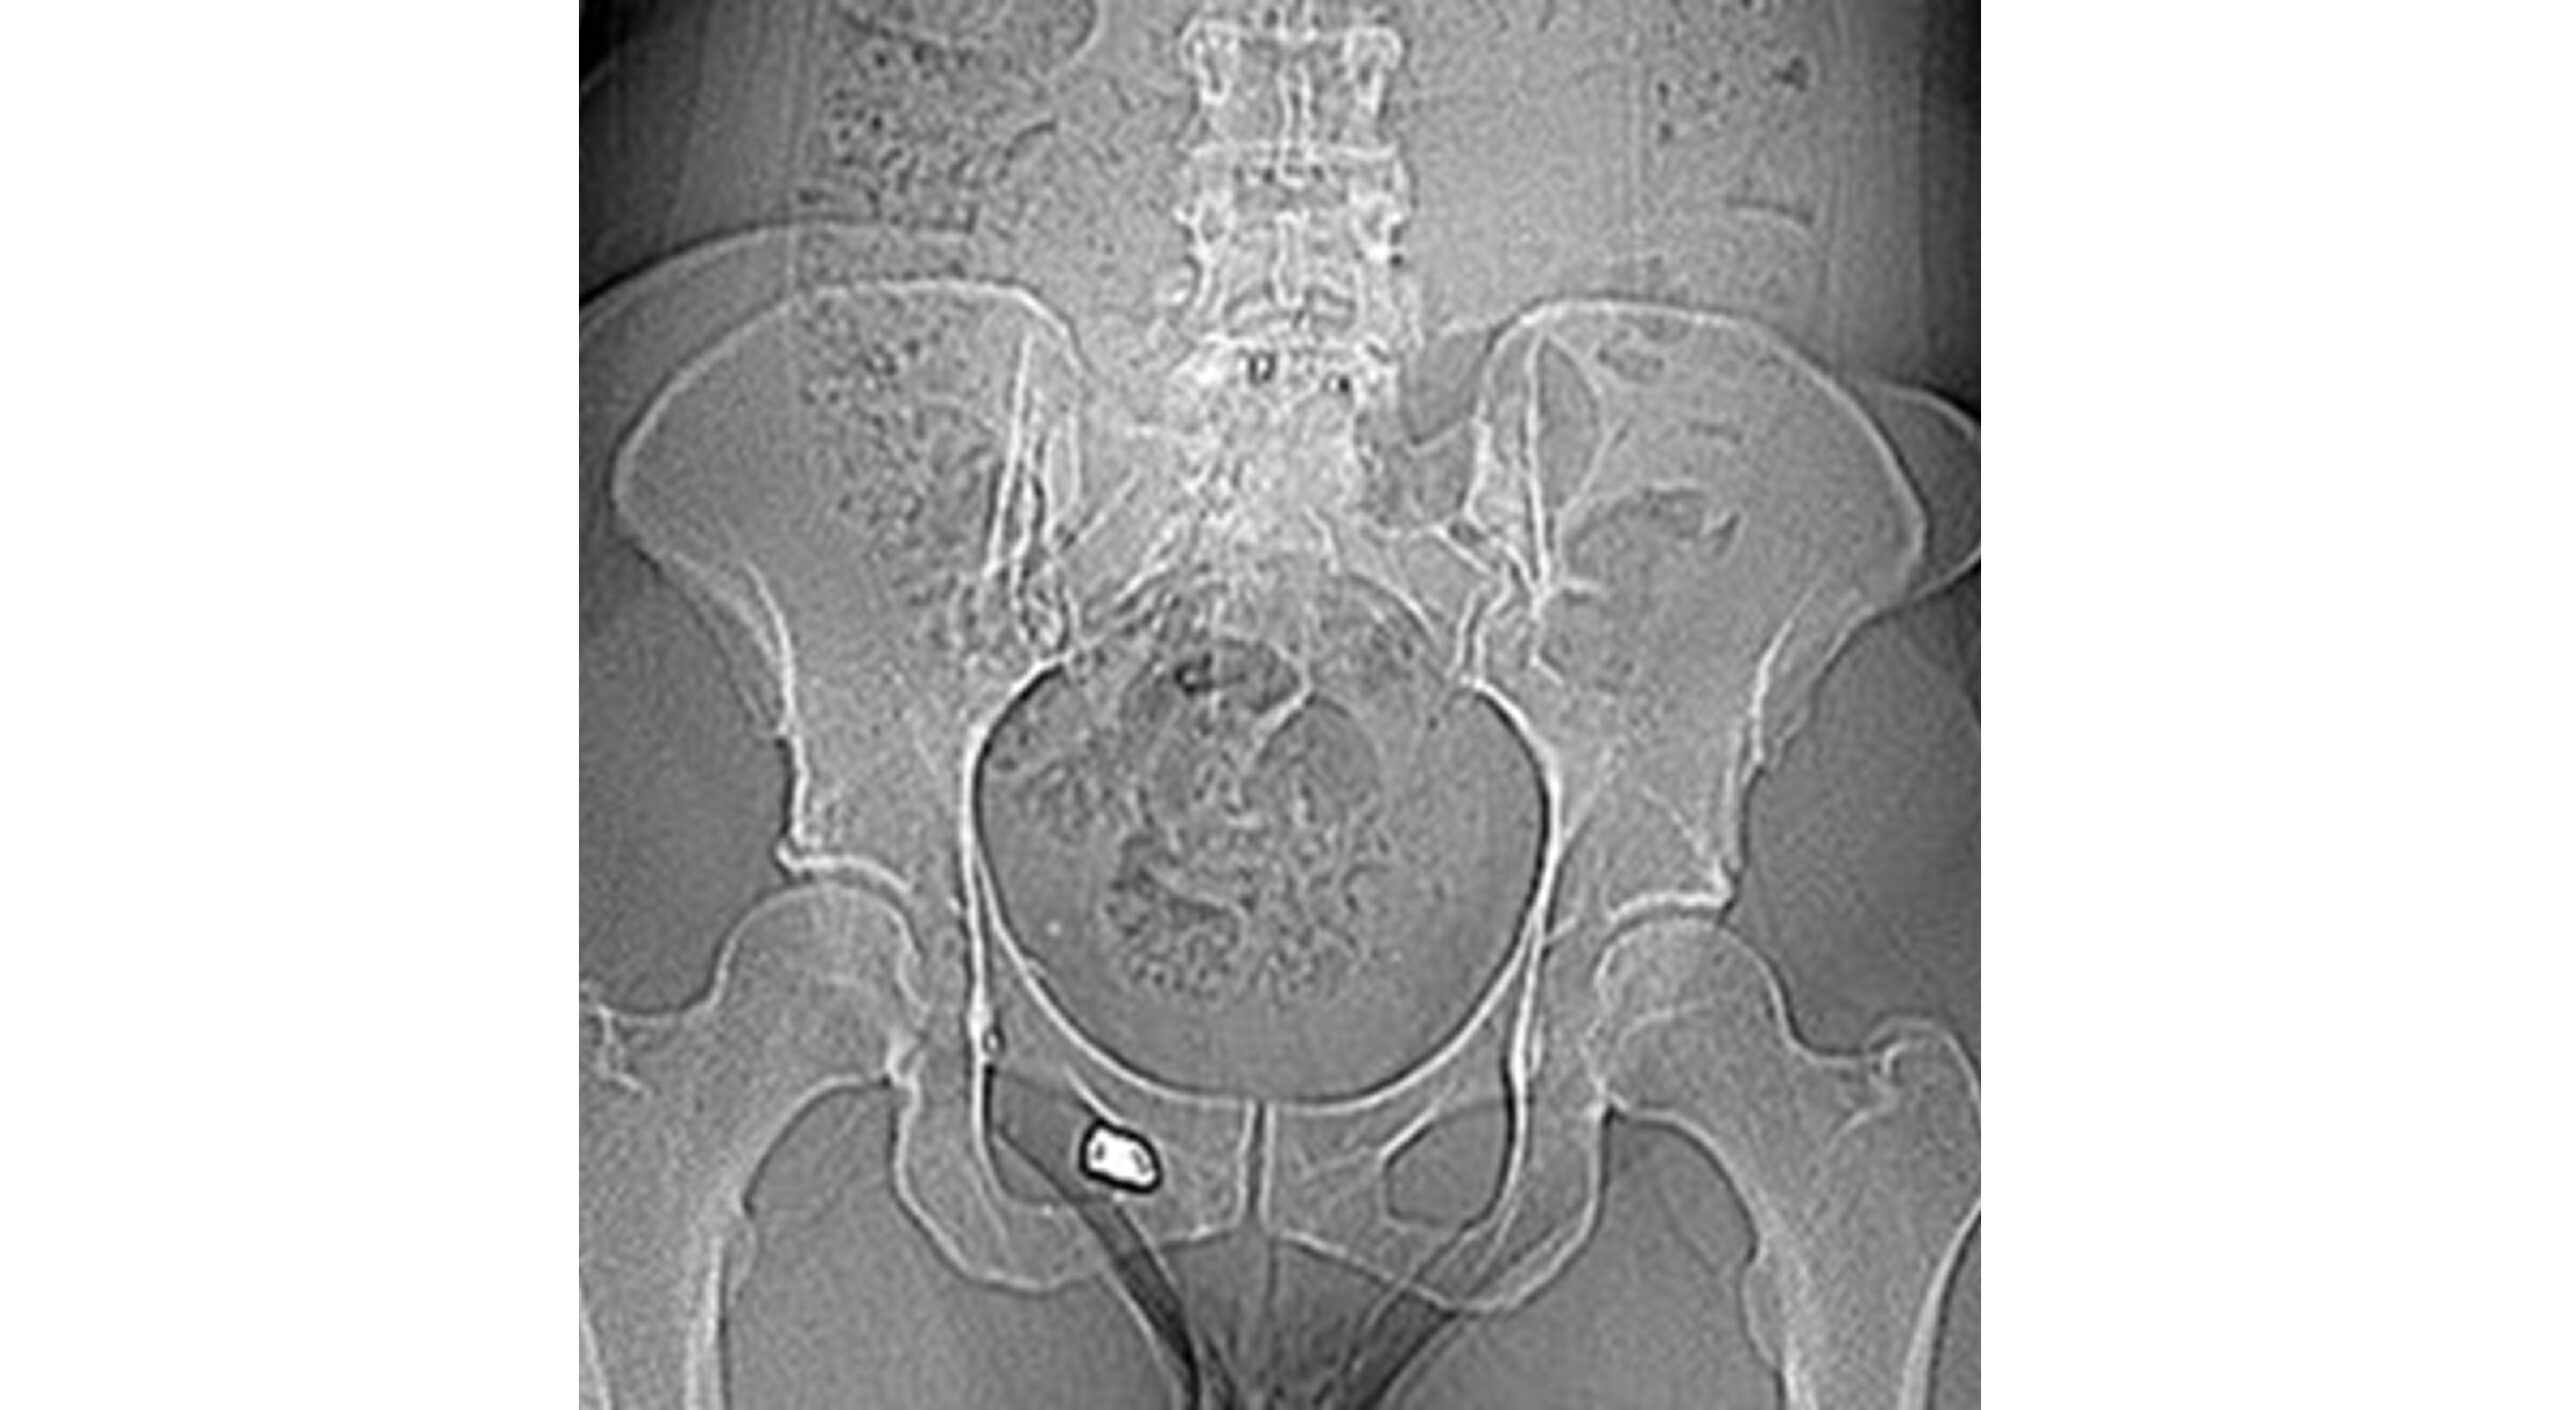

The patient’s primary care provider ordered venous lead testing due to bilateral hand and finger tingling, which revealed elevated lead levels of 17 ug/dL and 15 ug/dL at 7 months and 11 months post-GSW, respectively. Imaging included pelvic and lumbar spine X-rays and CT at 7.5 months post-injury that demonstrated the largest bullet fragment lodged in the right perirectal fat and another fragment in the obturator foramen, many metallic foreign bodies in chronic comminuted fractures of L5-S1, and a 3.2 cm cystic collection in the right anterior sacrum abutting the thecal sac (see Figures 1 and 2).

Figure 2: AP Pelvis X-ray demonstrating the main bullet fragment of the right obturator foramen. Lead fragments in L5-S1. Constipation and lead fragments in a cystic collection abutting the right anterior sacrum